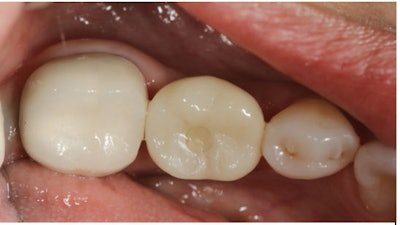

The hybrid crown was then tried in to verify occlusion and proximal contacts. (Figure 12). Once confirmed, the screw-access channel was sealed using Clearfil Majesty ES-2 composite to maintain aesthetics and function (Figure 13).

Figure 12: The screw-access channel with crown attached.

Figure 13: The screw-access channel was sealed using Clearfil Majesty ES-2 composite to maintain aesthetics and function.